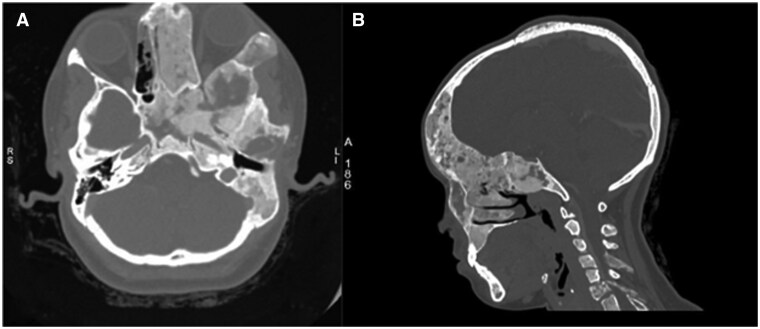

Fibrous dysplasia (FD) is a benign condition affecting osteoblasts, which fail to undergo proper differentiation and maturation, resulting in the replacement of normal osteoid matrix with ground glass fibrous tissue. Aneurysmal bone cyst (ABC) is a benign, expansile, lytic lesion characterized by multiple blood-filled cystic cavities containing haemorrhagic products at varying stages. Secondary ABC arising from craniofacial FD is extremely rare. To date, only 10 cases have been reported in the literature. This report highlights the clinical presentation, imaging findings, and histopathological confirmation of a secondary ABC in a patient with polyostotic craniofacial FD.